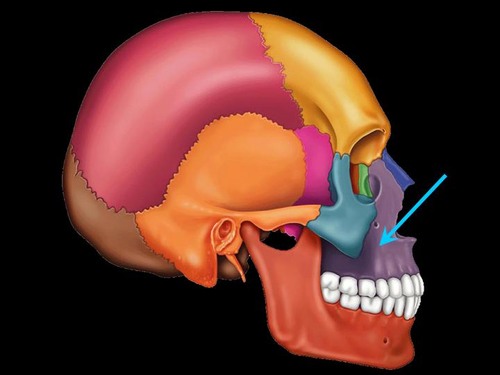

frontal bone

parietal bone

sphenoid bone

nasal bone

zygomatic bone

vomer bone

frontal maxilla

mandible

saggital suture

coronal suture

squamous suture

lambdoid suture

sphenoid bone (lateral view)

temporal bone

maxilla (lateral view)

zygomatic bone (lateral)